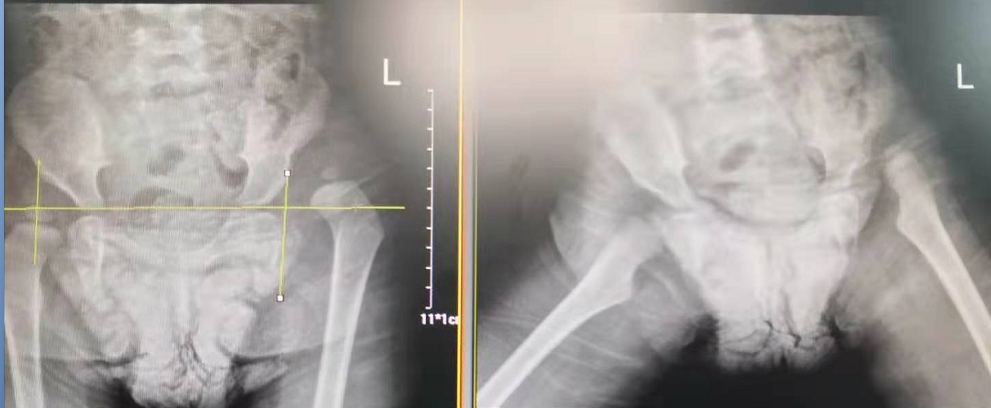

术前

术后